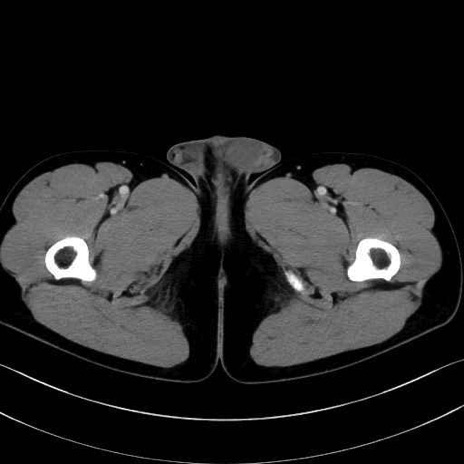

中殿筋 (Gluteus medius)